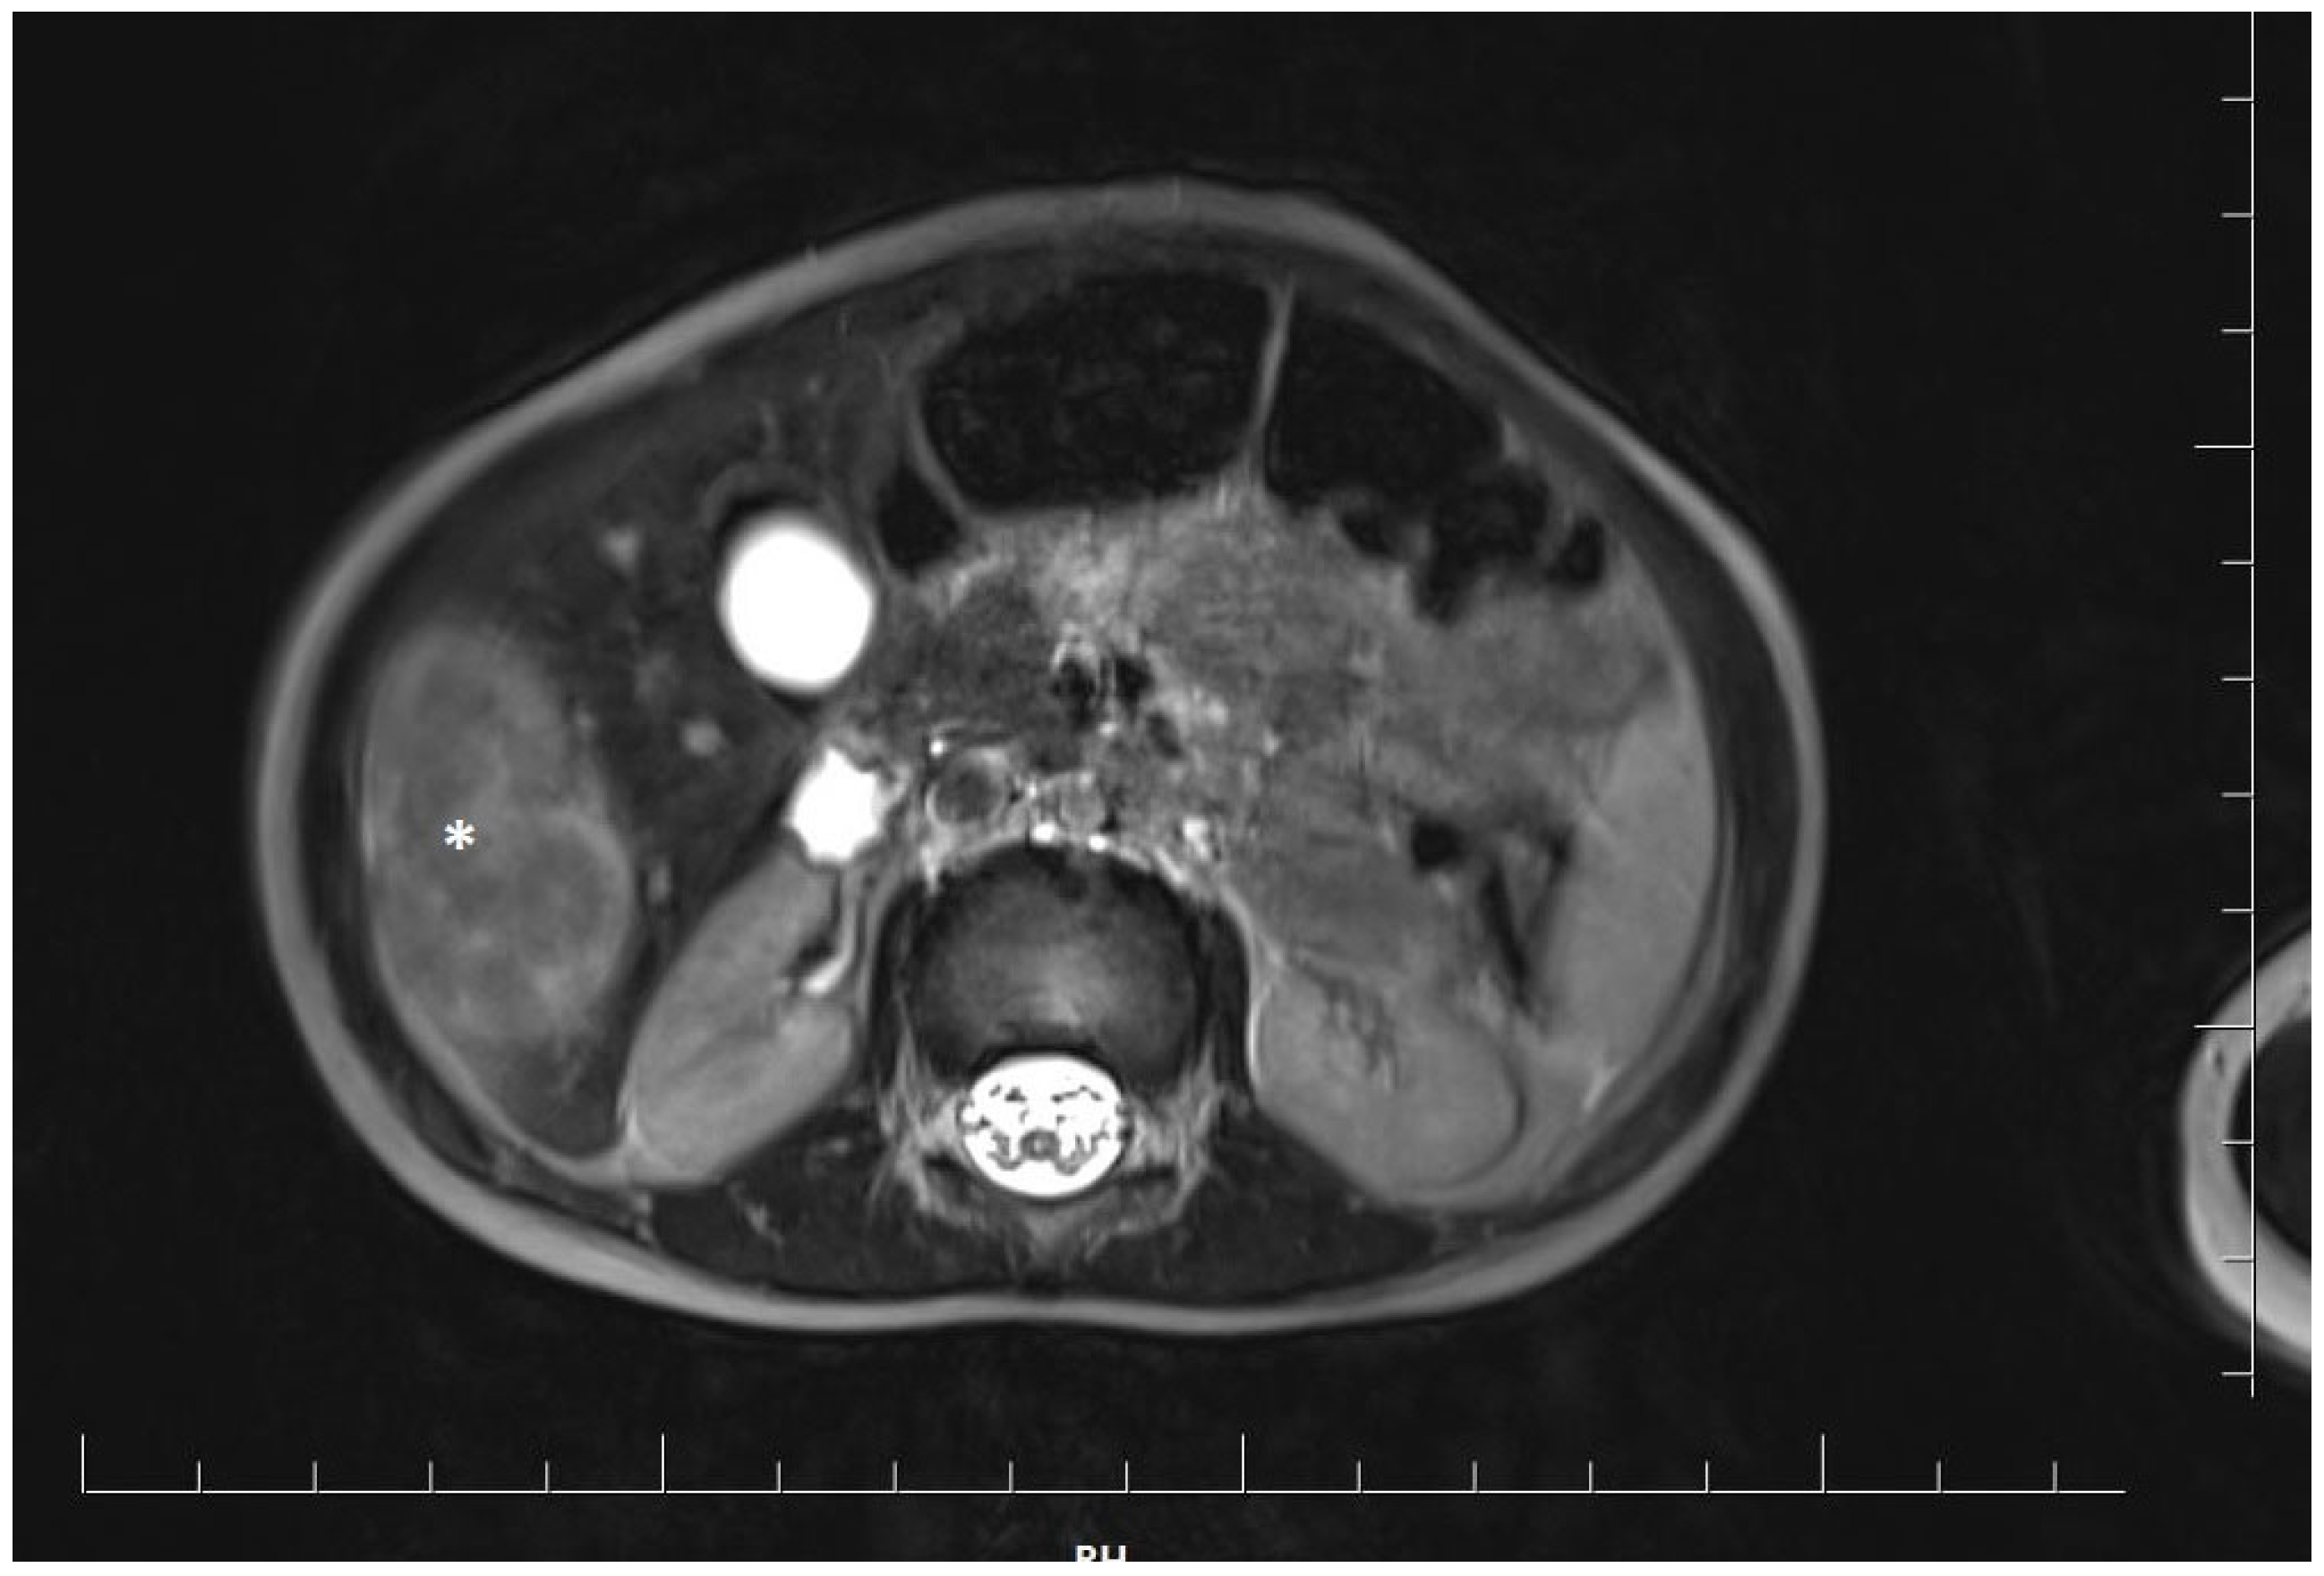

2. Case Report